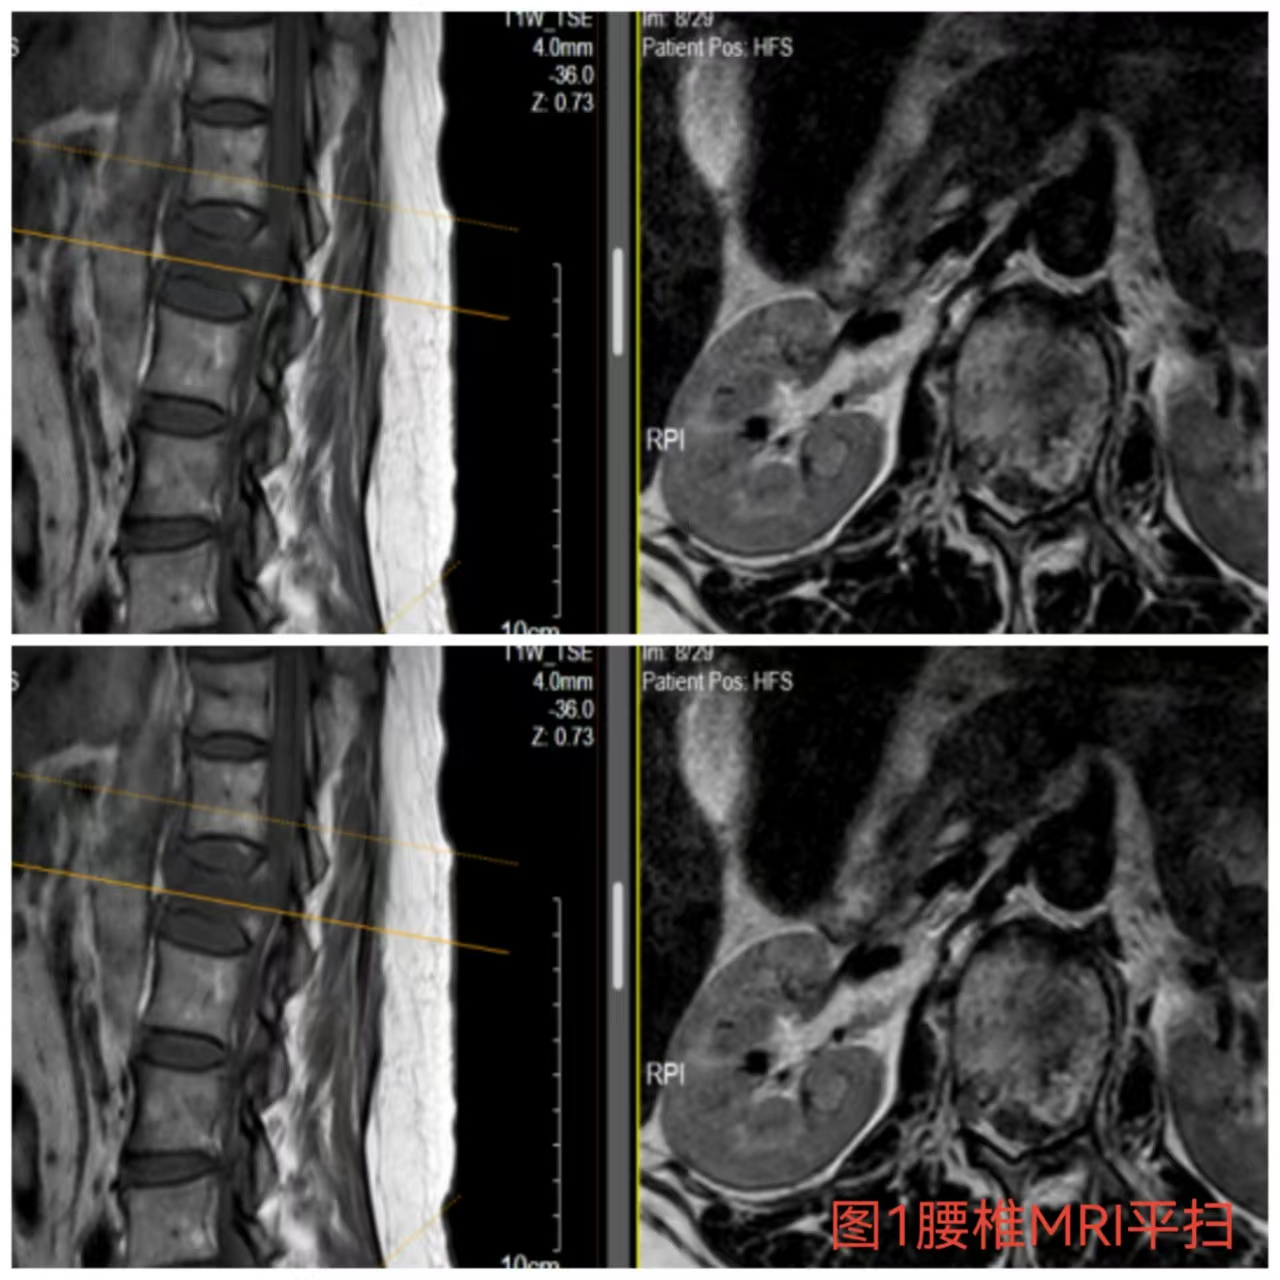

入院时患者躺在床上不可转动,,,,眼神中透漏着深深的无助,,,,关于她来说这种伤情无疑是极重的,,,,尤其是腹股沟以下感受消逝、双下肢肌力0级,,,,这意味着其下肢无法活动及站立,,,,似乎被运气按下了暂停键;;与病人及眷属充分相同病情后,,,,第一时间给予对症治疗,,,,监测患者生命体征,,,,行腰椎核磁检查(图1)提醒:腰1椎体爆裂性骨折,,,,椎体后缘塌陷致骨性椎管狭窄,,,,榨取脊髓神经,,,,连系患者病情及辅助检查可诊断为:“L1椎体爆裂性骨折伴双下肢截瘫”。。。。

俞德亮副主任医师深知病情的严重性,,,,拖得时间越久,,,,脊髓神经损伤症状越难以恢复,,,,必需掌握住早期减压手术的要害时间窗,,,,紧迫向导创伤骨科医师团队对该病情举行讨论、制订手术方案,,,,并乐成为患者急诊行“L1椎体爆裂性骨折伴截瘫切开椎板切除+椎管探查减压+骨折复位钉棒系统内牢靠术(图2)”,,,,该手术准确扫除对脊髓神经的榨取,,,,并通过椎弓根螺钉内牢靠系统对受损的腰椎提供稳固的支持,,,,为后期的康复创立了优异的条件。。。。